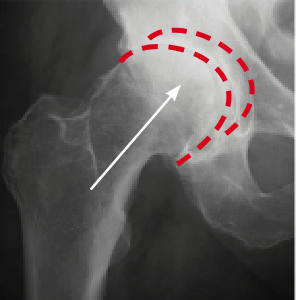

Снимката вляво (направена преди терапията) показва дефицит на синовиална течност, която причинява костна абразия. На снимката вдясно, благодарение на терапията, костите се движат плавно и безболезнено. Структурата на синовиалната течност се е възстановила – тя е възвърнала плъзгащите си свойства.

Зиглер доказа (както се вижда от рентгенови лъчи и ултразвук), че неговата антиартритна формула влияе върху регенерацията на ставите на три основни нива: